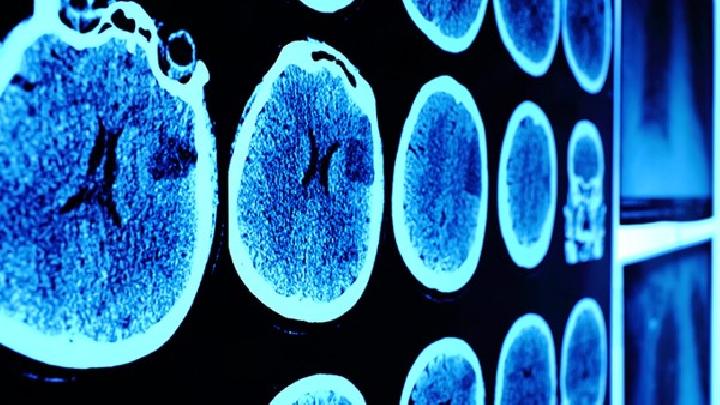

2.颅脑清创:颅脑火器伤无论是穿透伤还是非穿透伤,原则上都要早期彻底清创。

3.特殊类型伤害的治疗: